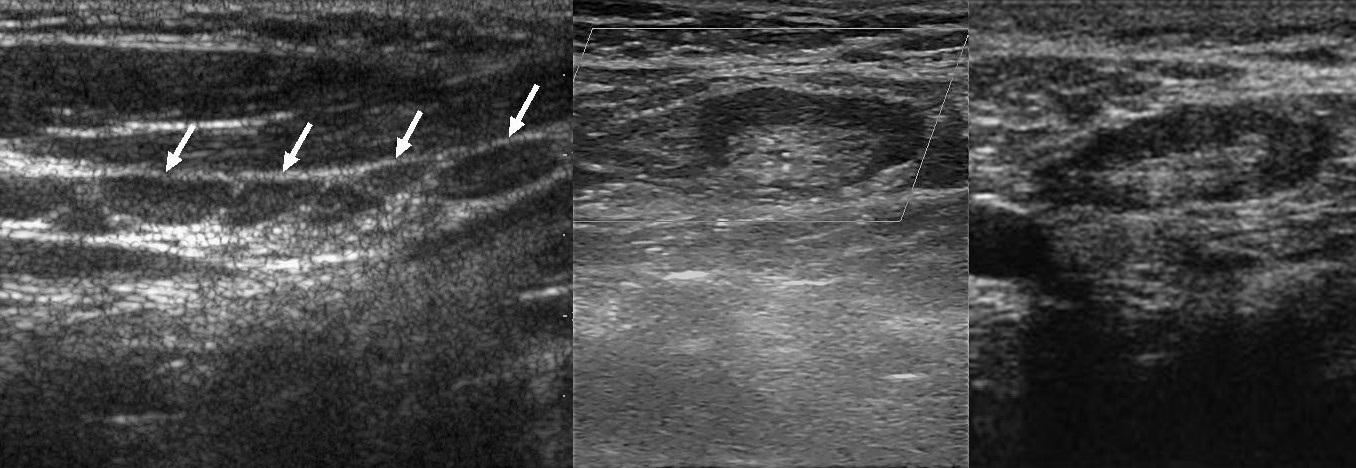

УЗИ лимфоузлов при лимфоме Ходжкина